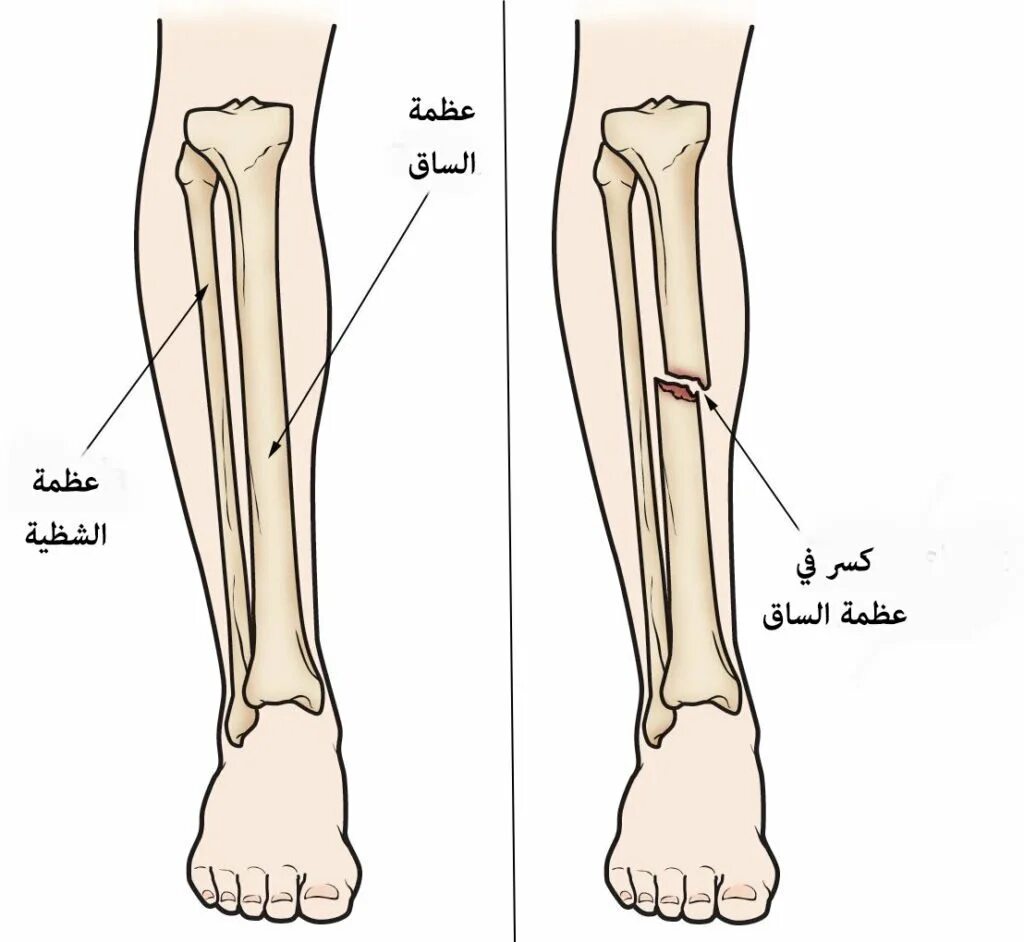

Перелом берцовой кости как разработать